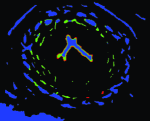

Appearance is one of the most important visual cues to distinguish between different structures in an image. Appearance is described by studying the distribution of different features such as intensity values in gray-scale images, color, and texture inside each object. In most cases, appearance models are incorporated into the data term in (2) and (7). The purpose of incorporating appearance prior is to fit the appearance distribution of the segmented objects to the distribution of objects of interest, e.g. using Gaussian mixture model (GMM) (Rother et al., 2004). In the literature, there are two ways to model the appearance: 1) adaptively learning the appearance during the segmentation procedure, and 2) knowing the appearance model prior to performing segmentation (e.g. by observing the appearance distribution of the training data). In the former case, the appearance model is learned as the segmentation is performed (Vese and Chan, 2002) (computed online). In the second case, it is assumed that the probability of each pixel belonging to particular label is known, i.e. if represents a particular set of feature values (e.g. intensity/color) associated with each image location for object, then it is assumed that is known (or pre-computed offline). This probability is usually learned and estimated from the distribution of features inside small samples of each object. Figure 9 illustrates the probability of different structures (the kidney, the tumour, and the background) in an endoscopic scene. A lower intensity in Figures 9(b-d) corresponds to higher probability.